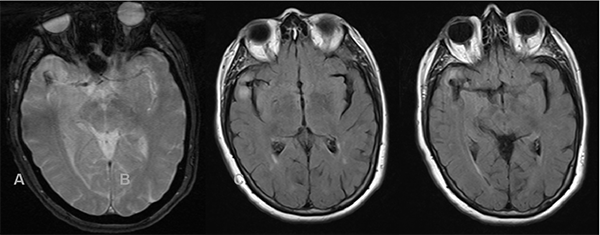

Paciente femenina de 72 años de edad con antecedentes de hipertensión arterial, dislipidemia, sobrepeso y extabaquista, a quien en contexto de estudio por hipoacusia neurosensorial se le realizó RM de cerebro y conductos auditivos internos con contraste endovenoso, en la cual se observó como hallazgo incidental lesión expansiva marcadamente hipointensa en T2 localizada a nivel temporal anterior derecho de aproximadamente 23 x 14 mm de diámetro en relación con el sector distal de la arteria cerebral media homóloga. Tras la inyección de contraste presentó refuerzo heterogéneo, con un componente de aspecto trombosado en el sector basal de la misma, asociado a extenso edema periférico (Figura 3). Se decidió realizar consulta con especialidad de neurocirugía quien sugirió completar la aproximación diagnóstica con AD de vasos intracraneanos en la cual se observó a nivel silviano derecho dilatación aneurismática de contornos lobulados con diámetros de 10.7 x 9.7mm, no presentando un cuello favorable para el acceso endovascular (Figura 4 y 5). En dicho estudio se menciona además pequeño aneurisma de 2mm en arteria comunicante anterior y otro silviano izquierdo de 4mm.

Figura 5: Estudio por AD, reconstrucción 3D del aneurisma descripto en Figura 4.